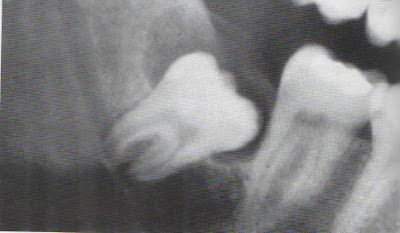

Grande lesão multilocular na mandibula, um terceiro molar impactado está localizado próximo ao angulo damandibula.

Ameloblastoma unicístico associado a um terceiro molar não erupcionado.

Radiograficamente a lesão assemelha-se a um típico cisto dentígero.

Ameloblastoma unicístico grande associado a um terceiro molar impactado, que causa significativa destruição do ramo ascendente.